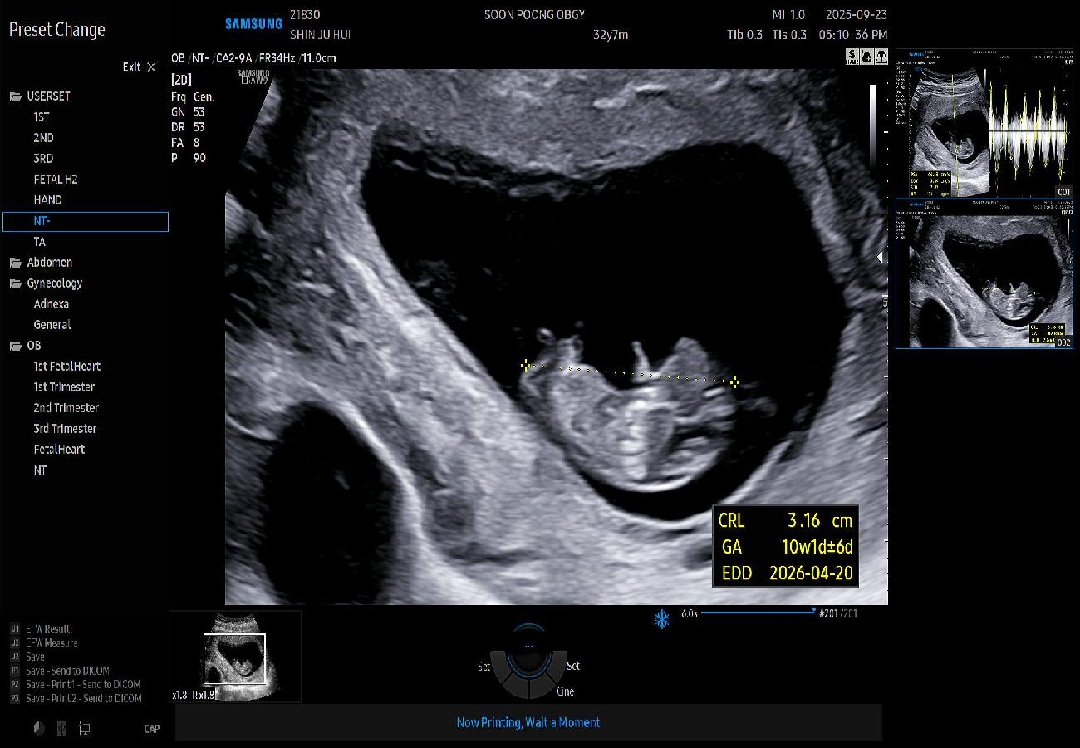

9주 6일입니다. 보통 기형아검사는 12주에 힌다고 알고 있었는데 제가 다니는 병원은 10주에 하네요. 원래 10주에도 하는건가요? 10주4일인 다음주 화요일 예정입니다. 니프티랑 중에 선택해서 오면 기본 기형아검사는 추석연휴에 결과 니온다더라고요. 3번의 자연유산후 4번째 임신이어서 임테기 확인하자마자부터 배주사(크녹산) 맞고 있고 이건 계속 맞자고 해요. 유산방지질정은 10주되는 내일까지만 쓰라고 하시네요 콩주사는 2주마다 맞아서 2번정도 맞았어요. 피린계알러지가 있어서 아스피린 처방은 못했구요. 이번에는 산전휴가를 당겨써서 한달간 정말 누워만 생활했습니다.